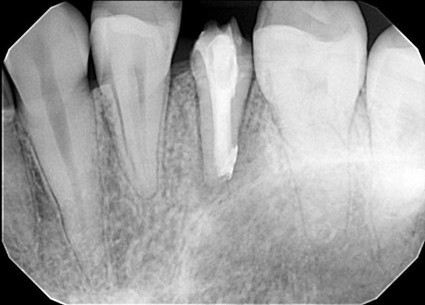

| 主訴 | 歯がしみる・見た目を改善したい |

| 状態 | 完全に神経が見えている状態だったので、根管治療を行ったのちセラミックで審美回復した症例。 |

| 料金 | 根管治療9万円+税、ファイバーコア2万円+税、仮歯1.5万円、E=MAXクラウン11.5万円+税(1本)×2本分=48万円 |

※根管治療と審美は別っていう医院が多いけど、包括的に治療できることが強み